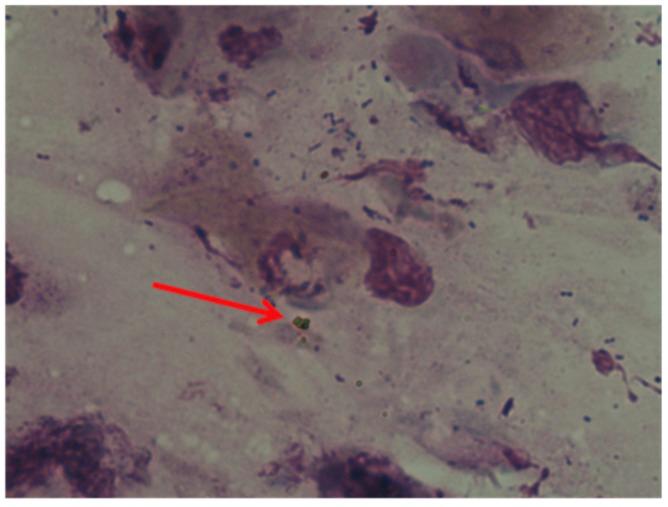

Nasal polyposis is characterized by benign, non-cancerous and painless growths originating in the tissue of the nasal cavities and paranasal sinuses. Polyps arise from chronic inflammation due to asthma, recurrent infections, allergies, drug sensitivity or immune disorders. They can obstruct the nasal cavities and thus cause respiratory problems, a reduction in the sense of smell and susceptibility to infections. Furthermore, nasal polyps can recur. Hence the importance of using valid diagnostic methods. In this work, the diagnostic investigation carried out by scanning electron microscopy (SEM) and nasal cytology led, for the first time, to the identification of a mycoplasma superinfection on nasal polyposis.

鼻息肉病的特征是鼻腔和鼻窦组织中出现良性、非癌性且无痛的肿物。息肉由哮喘、反复感染、过敏、药物敏感性或免疫紊乱引起的慢性炎症所致。它们会阻塞鼻腔,进而引发呼吸问题、嗅觉减退以及易感染。此外,鼻息肉会复发。因此,使用有效的诊断方法至关重要。在这项研究中,通过扫描电子显微镜(SEM)和鼻腔细胞学进行的诊断调查首次发现鼻息肉病存在支原体二重感染。